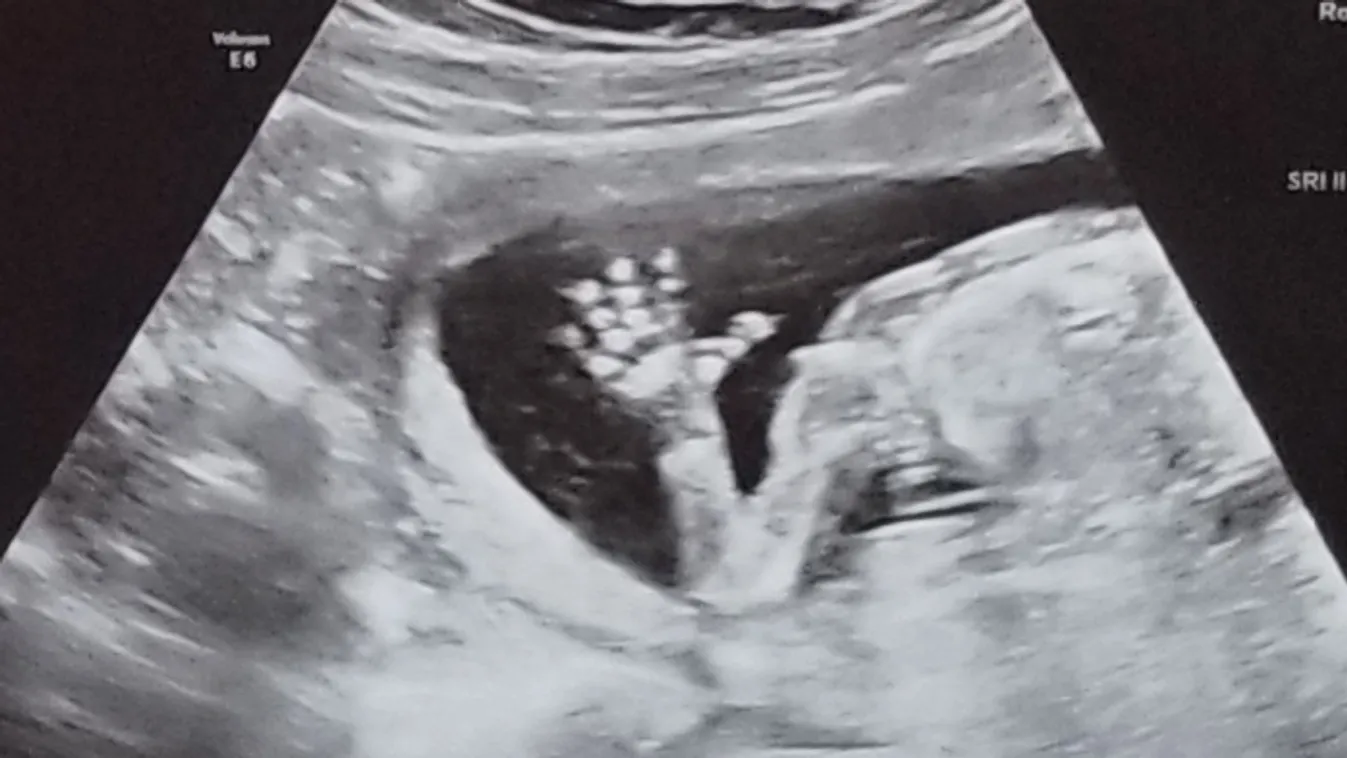

A Michigan-i nő a szokásos rutinvizsgálatra ment a nőgyógyászához, többek között ultrahangra is. A 27 éves Bethany McMillin döbbenten hallotta orvosától, hogy nem csupán két vaginája, de két méhe is van.

Ami azért is rémítette meg, mert az első terhességével elvetélt, és nagyon szerettek volna férjével még egy babát; de a ritka rendellenesség miatt félő volt, hogy soha nem lesz képes életet adni egy gyermeknek.

Amikor egy évvel később teherbe esett, végül sikeresen kihordta a magzatot, és egészséges gyereke született. Bethany most azért állt a nyilvánosság elé, hogy beszéljen arról, milyen ezzel a ritka rendellenességgel élni – hiszen jócskán akadnak még nők a világon, akiknek két méhe és hüvelye van, és édeskevés információ van arról, hogyan lehet kezelni az állapotot.